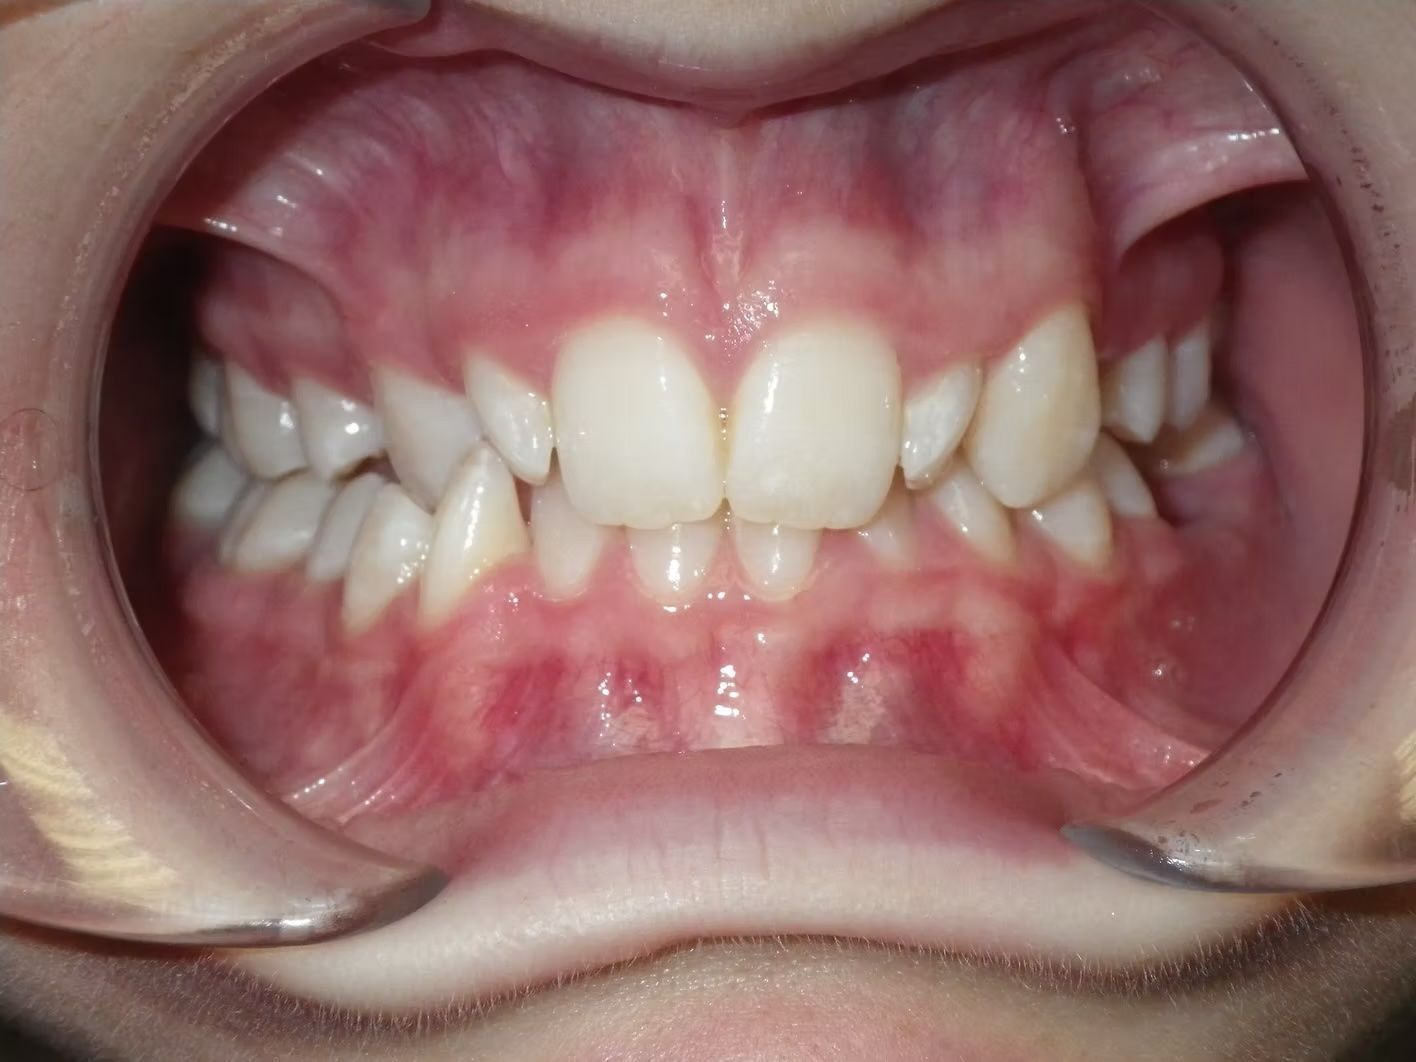

IAN

Ian came to the office because his lower teeth were crowded and he had an anterior cross bite. With traditional braces we resolved the crowding and aligned the teeth without causing flaring of the incisors and giving him a handsome smile. The treatment lasted 18 months and the final photos are at a 2 year follow up when we made him a new clear retainer.